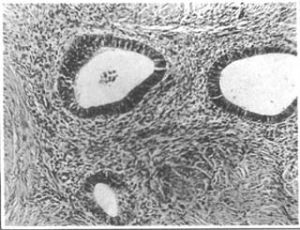

一、内在性子宫内膜异位症 内膜由基底部向肌层生长,局限于子宫,故又名子宫腺肌病。异位的子宫内膜常弥散于整个子宫肌壁,由于内膜侵入引起纤维组织及肌纤维的反应性增生,使子宫一致性胀大,但很少有超过足月胎儿头大者。不均匀或局灶型分布者一般以后壁多见,由于局限在子宫一部,往往使子宫不规则增大,酷似子宫肌瘤。切面可见增生的肌组织亦似肌瘤呈漩涡样结构,但无肌瘤所具有与周围正常肌纤维分开的包膜样组织(照片1)。病灶中间有软化区,偶可见到散在的含有少量陈旧积血的小空腔。镜检所见的内膜腺体与子宫内膜腺体相同,其周围由内膜间质所包绕(照片2)。异位内膜随月经周期而改变,但分泌期改变不明显,表示异位的内膜腺体受孕激素影响较小。当受孕时,异位内膜的间质细胞可呈明显蜕膜样变,已如上述。

照片1 弥散性子宫腺肌病

照片2 子宫腺肌病组织象